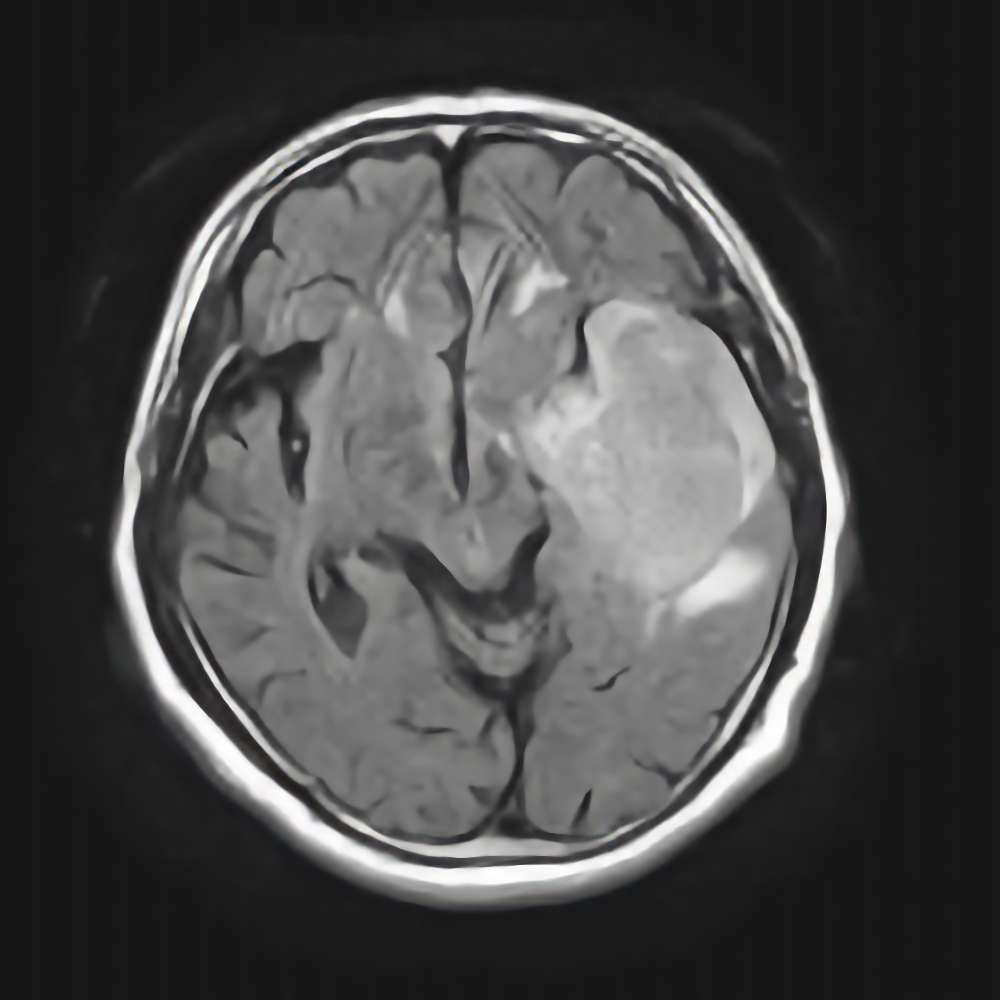

'15年12月

20代

細胞腫

(前頭葉星)

No.’15_180 手術前1

No.’15_180 摘出 前

No.’15_180 摘出 後